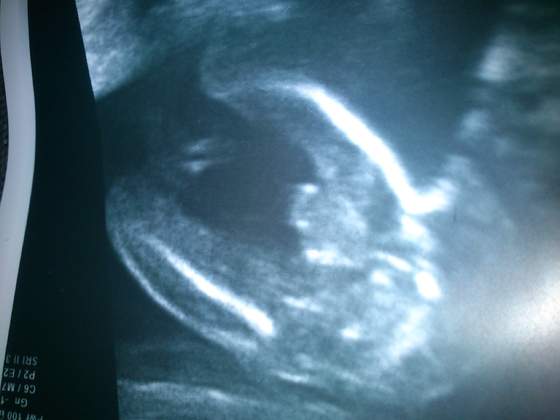

Piranhia napisałam Ci to wszystko w PW. Dietę stosowalam tylko ja. Oboje lykalismy suplementy z listy w podanych ilościach. Nie mierzylam poziomu hormonów i mierzylam i obnizalam PH az do owulacji. Imię już mamy. Kolejne USG w poniedziałek ale to raczej do sprawdzenia szyjki - dzidzia tez pewnie podgladniemy :). A USG polowkowe mam 25 listopada dopiero.